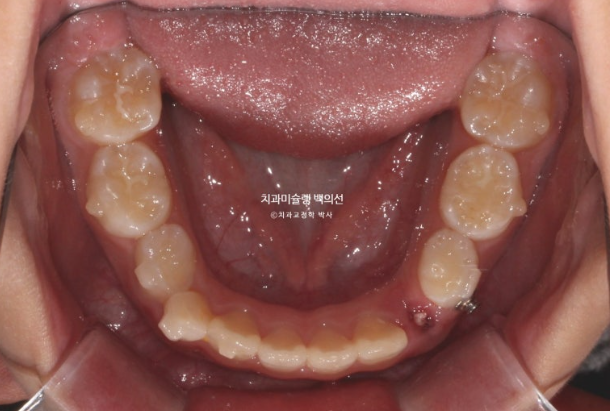

2025.5 드디어 치료를 마무리 했습니다.

중심선은 잘 맞으며

그사이 남은 유치들이 대거 빠지고 영구치 맹출을 기다리는 중입니다.

영구치가 다 나올때까지 유지는 뺏다꼈다 하는 가철식 유지장치를 사용키로 합니다.

아이가 아직 성장중인 만큼 꼼꼼한 사후관리가 필요합니다.

총 치료기간은 프리올소 2개월, 인비절라인 퍼스트 2년입니다.

성장을 이용한 비대칭 치료이니만큼, 최대성장기를 최대한 이용하기 위해 중간에 쉬는시간 없이 인비절라인퍼스트가 보증하는 보증기한동안 장치를 계속 착용했습니다.

비대칭은 개선되었으며 중심선은 맞아졌습니다.

앞니 교합은 좋습니다.